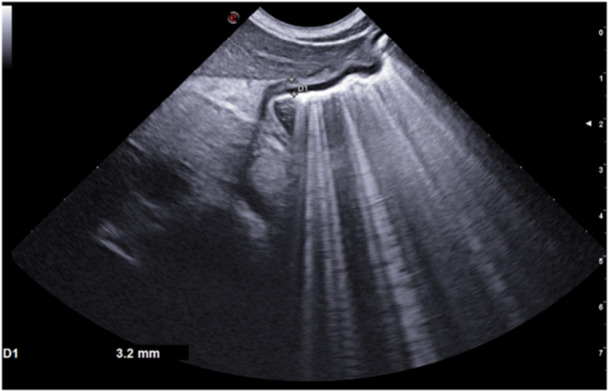

Menetrier's disease (MD) is a protein-losing gastropathy characterized by acute generalized edema due to hypoalbuminemia. MD is rare in childhood, and it is commonly associated with cytomegalovirus infection. We reported two children, who presented with a history of generalized edema after some days of abdominal pain and diarrhea. Laboratory tests showed hypoalbuminemia with no proteinuria. Thoracic and abdominal ultrasound (US) revealed respectively pleural and pericardial effusion and ascites. A specific gastric echography showed gastric wall thickening (>3 mm) and upper gastrointestinal endoscopy revealed prominent folds in the gastric body and fundus, with a subsequent histological confirmation of Menetrier diagnosis. They were discharged after several albumin infusions. A US follow-up confirmed the remission of the disease after 1 and 6 months. Gastric US revealed accurate in the diagnosis of this rare condition and in its follow-up. avoiding a second endoscopy in the short term.